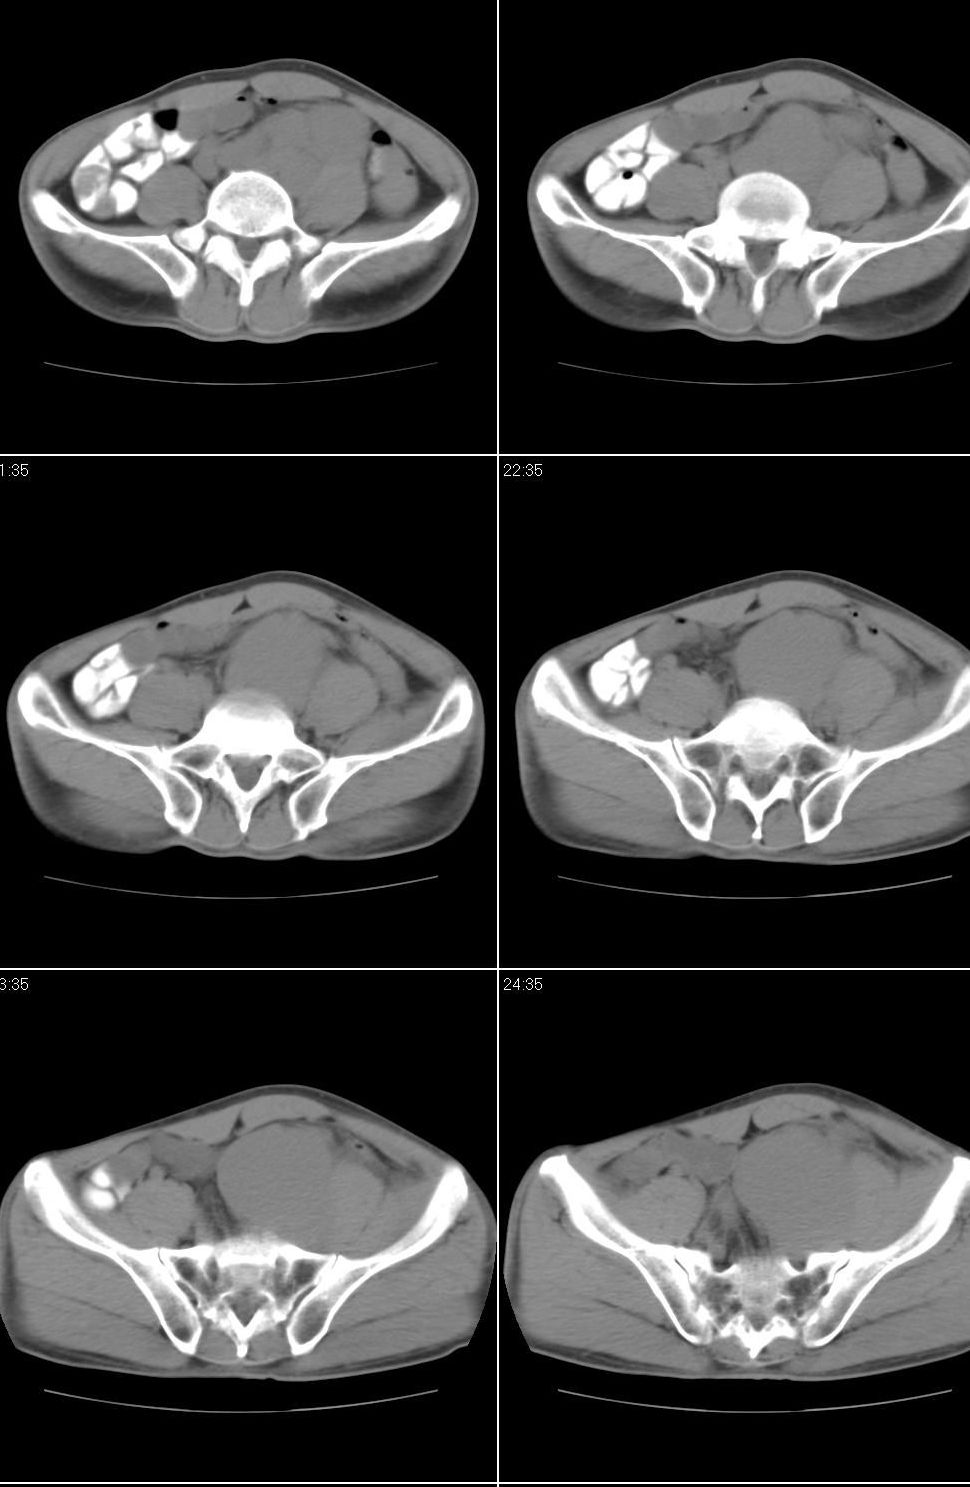

以下是引用jiangjing在2007-9-18 17:20:00的发言:[br]考虑生殖细胞肿瘤伴腹腔及腹膜后与腹股沟区淋巴转移,腹膜后大血管受压受侵

以下是引用老爱克斯新网客在2007-9-18 18:27:00的发言:[br]主动脉旁左侧腹股沟可见多发结节状病灶,1淋巴瘤,2转移瘤待除外,